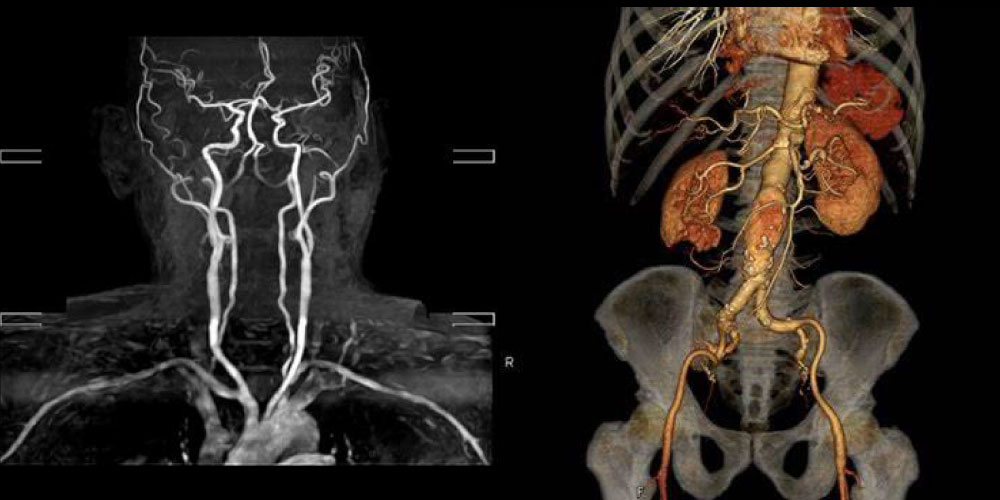

血管造影

造影剤を使用して血管を描出し状態を調べる検査で、当院では主に頭頸部血管や胸腹部血管を観察する為に行っています。

CT画像をコンピューター処理することにより、立体的な画像(3DCT)を作ることができます。

血管の形態が視覚的に理解でき、診断にも有用です。